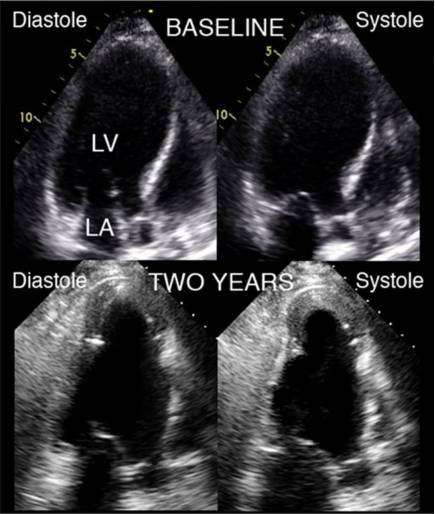

Echocardiagraphic image comparing baseline volume to 2-y follow-up functional volume:

Left ventricular end-diastolic volume index (LVEDVi) and end-systolic volume index (LV ESVi) mean±SD plotted over time:

39例伴有类似左室室壁瘤的缺血性心脏病患者,心功能Ⅱ-Ⅳ级,EF:15-40%之间;

结果:31/34/39成功植入器械,其中23人随访了3年,85%患者有心功能或症状改善,收缩或舒张末期容积指数明显下降,3年内有38.7%患者再入院或死亡事件,仅2人死于心脏原因;

结论:Parachute是安全有效的。